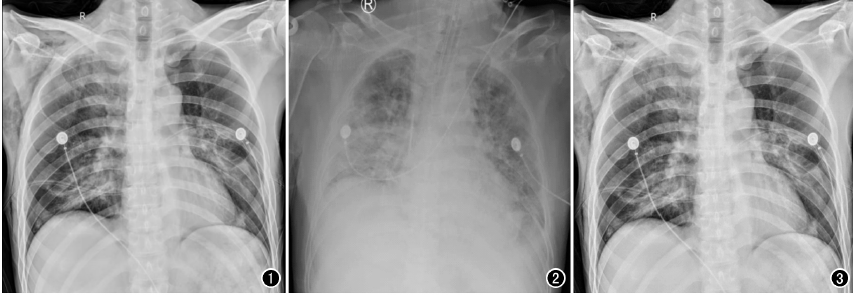

以心臟手術(shù)為例,開胸心臟手術(shù)多數(shù)是在低溫、全麻和體外循環(huán)下進(jìn)行,胸腔創(chuàng)傷較大、風(fēng)險(xiǎn)極高,心臟術(shù)后,心外科醫(yī)師為了能及時(shí)了解術(shù)后患者的雙肺復(fù)張情況、氣管插管導(dǎo)管頭端位置以及手術(shù)并發(fā)癥等情況,需要及時(shí)對(duì)患者進(jìn)行胸部X線片檢查,以便觀察氣管插管位置,一般來說,插管位置下端應(yīng)位于第3胸椎水平,過深或者過淺都將影響呼吸機(jī)的輔助效果,應(yīng)確保位置準(zhǔn)確,以免影響通氣狀況。另外,包括對(duì)于相關(guān)手術(shù)并發(fā)癥的檢查,包括:胸腔積液、氣胸、肺不張等常見問題,需要及時(shí)進(jìn)行胸部X光檢查。相較于幾百萬像素的移動(dòng)DR,百微移動(dòng)DR,在圖像質(zhì)量上顯示更清晰,檢查效率更高,更利于醫(yī)生及時(shí)進(jìn)行處置。